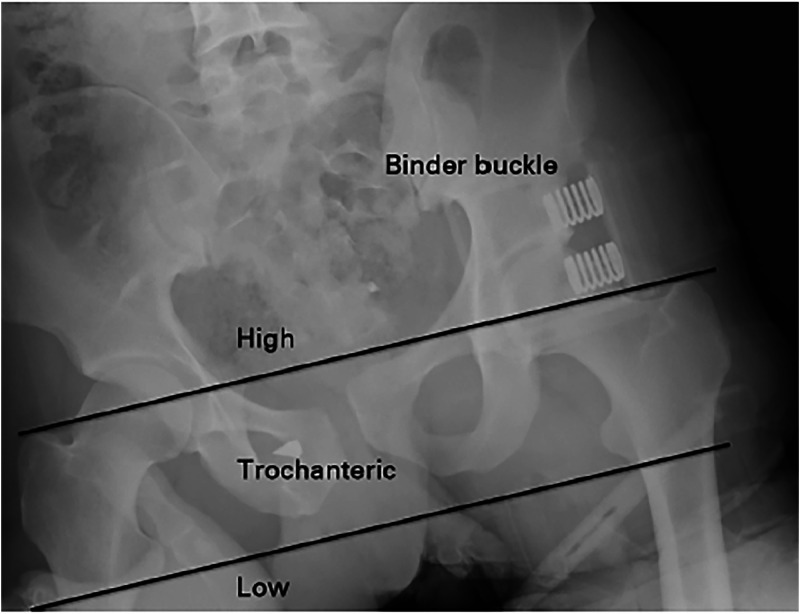

Unstable pelvic fractures cause significant bleeding, morbidity, and mortality. Commercially available Pelvic Circumferential Compression Devices (PCCDs) are used in the initial resuscitation and management of these cases. In the trauma-burdened, resource limited setting of Southern Africa, the available alternative is a pelvic sheet binder (PSB). For optimal results placement should be at the greater trochanters (GTs). Prior studies have shown that practitioners are inaccurate in their placement. This study aimed to describe placement of PSBs by doctors and factors influencing placement.

This was a multicentre, prospective, observational, simulation-based study. Doctors working in Emergency Departments (EDs) and Trauma Emergency Units (TEUs) in Johannesburg were asked to place a PSB on two healthy male models of differing body mass index (BMI), as simulated patients (SPs). Outcomes were based on PSB position relative to the GTs, marked using an ultraviolet pen, and photographed under ultraviolet light. Data on techniques of placement, as well as practitioner factors, were also collected to investigate their influence on accuracy.

In this study 147/176 (83.5 %) of the PSBs placed were correct (trochanteric). Of those placed on the normal BMI SP 71/88 (81 %) were correct and 76/88 (86 %) of those on the increased BMI SP. BMI did not appear to influence accuracy of placement. Practitioner factors that had statistically significant association with accurate placement included the following: Working in the TEU, work experience of ≥6 years, a diploma in primary emergency care (DipPEC, College of emergency medicine, South Africa), all methods of placing the PSB and inspecting to find the GTs.